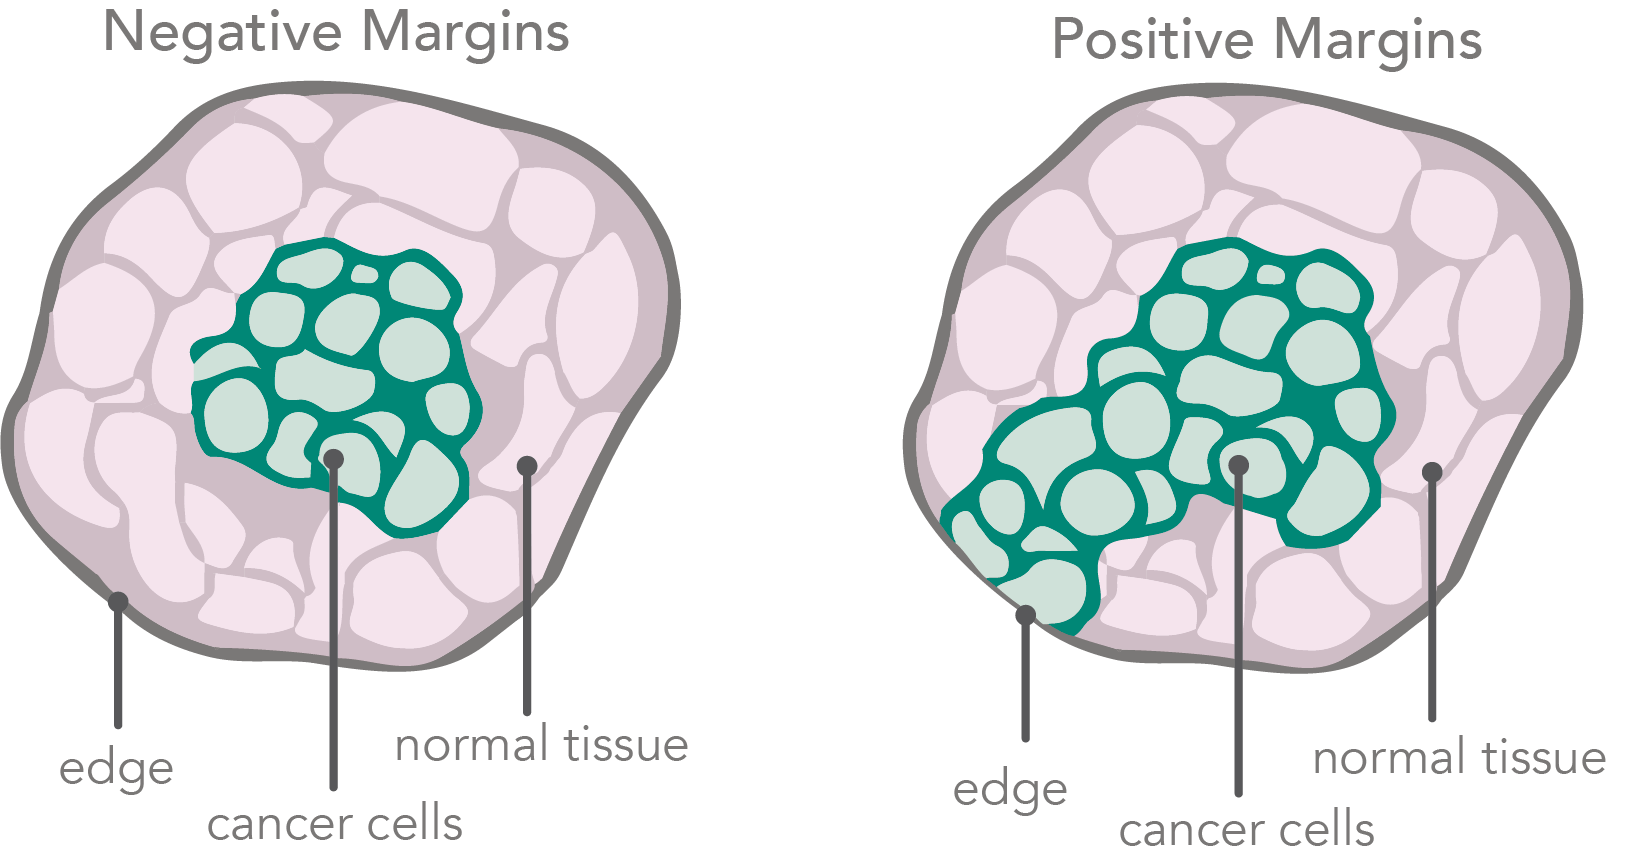

Guide To Understanding Surgical Margins | KUBTEC

www.kubtec.com

New Evidence About Why Clear Margins In Breast Cancer Surgery Are Such

ourscience.info

evidence margins surgery breast cancer such clear why good

Margins In Breast Cancer: How Much Is Enough? – Pilewskie – 2018

acsjournals.onlinelibrary.wiley.com

margins